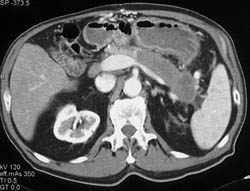

Pseudocyst With Septations